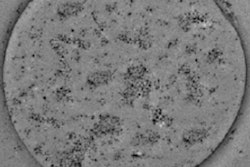

Zhang and colleagues first characterized the SPIO-containing microbubbles (SPIO-MBs) using transmission electron microscopy. Images of a microbubble showed a uniform surface, while an SPIO-MB showed nanometer-scale dark dots on the bubble surface, verifying successful integration of SPIOs. Atomic force microscopy (AFM) revealed that a typical microbubble had a relatively smooth surface, while the SPIO-MB was larger and had a rougher structure, due to embedding of SPIOs onto the bubble shell.

(a) Transmission electron microscopy (TEM) image of microbubbles without the addition of nanoparticles; (b) TEM image of an SPIO-MB.The researchers assessed the microbubble sizes seen for SPIO concentrations in microbubble suspension of 0.0, 19.6, 114.7, and 292.0 µg/mL (groups 1-4, respectively). The mean microbubble diameter increased with increasing SPIO concentration, reaching about 3.5 µm for group 4, and indicating that the SPIO-MBs are small enough to function as effective clinical agents.